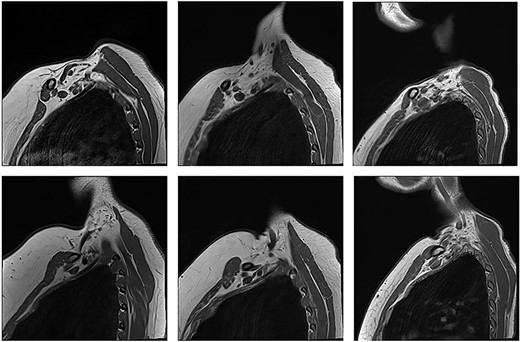

Unaffected patients. The top row are sequences with the arm in the neutral position. The bottom row is the corresponding patient with the arm raised.